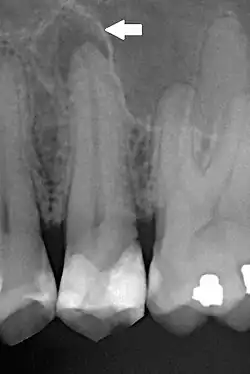

| Periapical dental radiograph showing chronic periapical periodontitis on the root of the left maxillary second premolar. Note large restoration present in the tooth, which will have undergone pulpal necrosis at some point before the development of this lesion. | |

Periapical periodontitis or apical periodontitis[9] (AP) is an acute or chronic inflammatory lesion around the apex of a tooth root, most commonly caused by bacterial invasion of the pulp of the tooth.[10] It is a likely outcome of untreated dental caries (tooth decay), and in such cases it can be considered a sequela in the natural history of tooth decay, irreversible pulpitis and pulpal necrosis. Other causes can include occlusal trauma due to 'high spots' after restoration work, extrusion from the tooth of root filling material, or bacterial invasion and infection from the gums. Periapical periodontitis may develop into a periapical abscess, where a collection of pus forms at the end of the root, the consequence of spread of infection from the tooth pulp (odontogenic infection), or into a periapical cyst, where an epithelial lined, fluid-filled structure forms.

The radiographic features of periapical inflammatory lesions vary depending on the time course of the lesion. Because very early lesions may not show any radiographic changes, diagnosis of these lesions relies solely on the clinical symptoms. More chronic lesions may show lytic (radiolucent) or sclerotic (radiopaque) changes, or both.